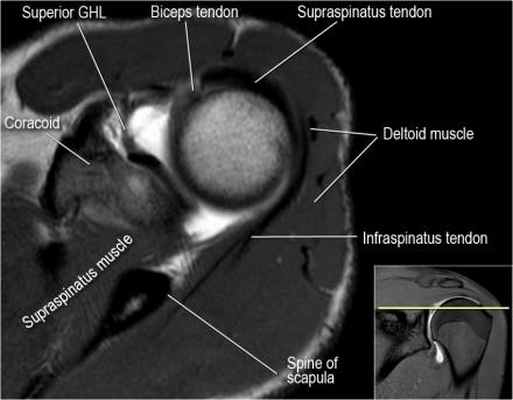

Нормальная анатомия плечевого сустава в аксиальных изображениях и контрольный список.

- поищите os acromiale, акромиальную кость (добавочная кость, расположенная у акромиона)

- обратите внимание что ход сухожилия надостной мышцы параллелен оси мышцы (это не всегда так)

- обратите внимание что ход сухожилия длинной головки двуглавой мышцы в области прикрепления направлен на 12 часов. Область прикрепления может быть различной ширины.

- обратите внимание на верхние отделы суставной губы и прикрепление верхней плече-лопаточной связки. На данном уровне ищется SLAP-повреждение (Superior Labrum Anterior to Posterior) и варианты строения в виде отверстия под сутавной губой (sublabral foramen - подгубное отверстие). На этом же уровне по задне-боковой поверхности головки плечевой кости визуализируются повреждение Хилл-Сакса.

- волокна сухожилия подлопаточной мышцы, создавая бицепитальную борозду, удерживают сухожилие длинной головки двуглавой мышцы. Изучите хрящи.

- уровень средней плече-лопаточной связки и передних отделов суставной губы. Поищите комплекс Буффорда. Изучите хрящи.

- вогнутость заднебокового края головки плечевой кости не следует путать с повреждением Хилл-Сакса, поскольку это нормальная форма для данного уровня. Повреждение Хилл-Сакса визуализируется только на уровне клювовидного отростка. В предних отделах мы сейчас на урвоне 3-6 часов. Здесь визуализируются повреждение Банкарта и его варианты.

- обратите внимание на волокна нижней плече-лопаточной связки. На данном уровне так же ищется повреждение Банкарта.